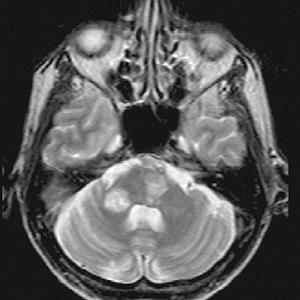

Muž, 61 let. Ischemie ve vertebrobazilárním povodí, dvakrát prodělal infarkt myokardu (IM), v anamnéze kardiomyopatie, hypertenze. Náhlá porucha vizu, nauzea, vomitus, hypakuze, vertigo, nemůže se sám postavit. Objektivní vyšetření: dezorientován, cerebelární syndrom vlevo, centrální vestibulární syndrom, levostranná hemiparéza.

Obr. A1.1–A1.4 Trombóza a. basilaris, akutní ischemické změny vertebrobazilárního povodí (pons, pedunculus cerebri medius dextra, parietookcipitální oblast).

Šipka v obrázku A1.2 – nezobrazilo se vertebrobazilární povodí